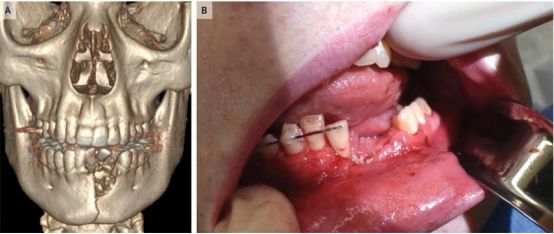

据NEJM的报道,美国犹他州的一家儿科医院接诊了一名17岁的少年,下巴处有圆形伤口,口腔内存在

大量撕裂伤,下切牙多处被破坏,甚至还检查出粉碎性下颌骨骨折。

而这些口内伤痕,全都是拜“祸水烟”所赐。这名美国少年在抽*子烟电**时,*子烟电**在其口腔内直接发生了

爆炸,并且,号称“无害”的*子烟电**并未发出任何警报。

被*子烟电**爆炸伤了口腔的17岁美国少年